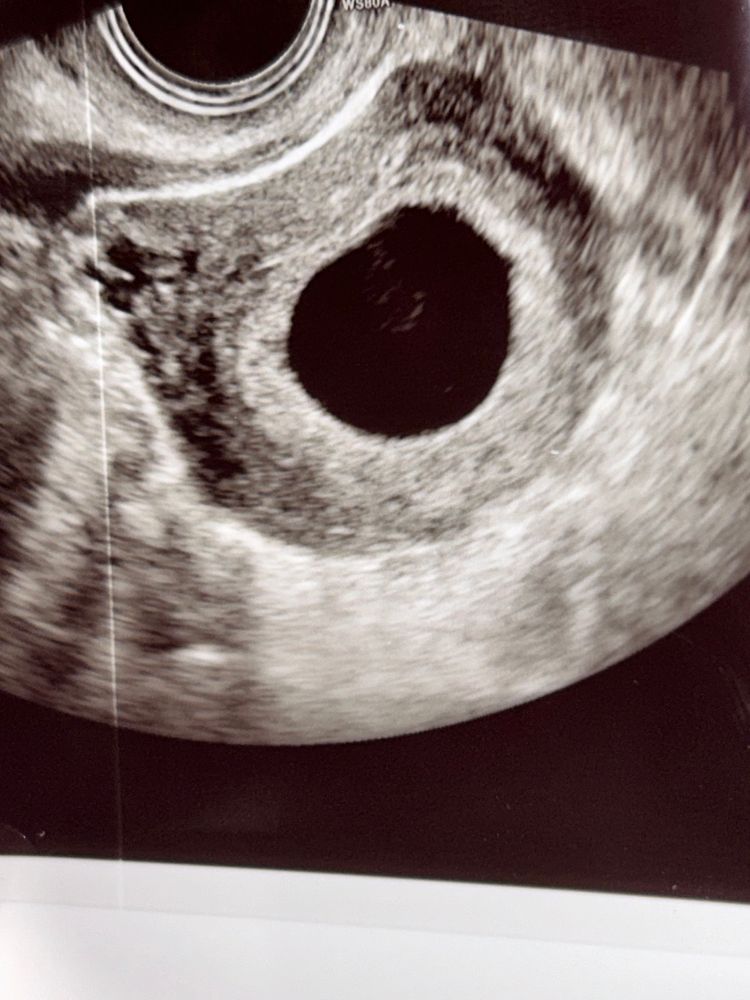

Что внутри плодного яйца ? 21 мм плодное , 6 нед 4 дня, ставят анембрионию